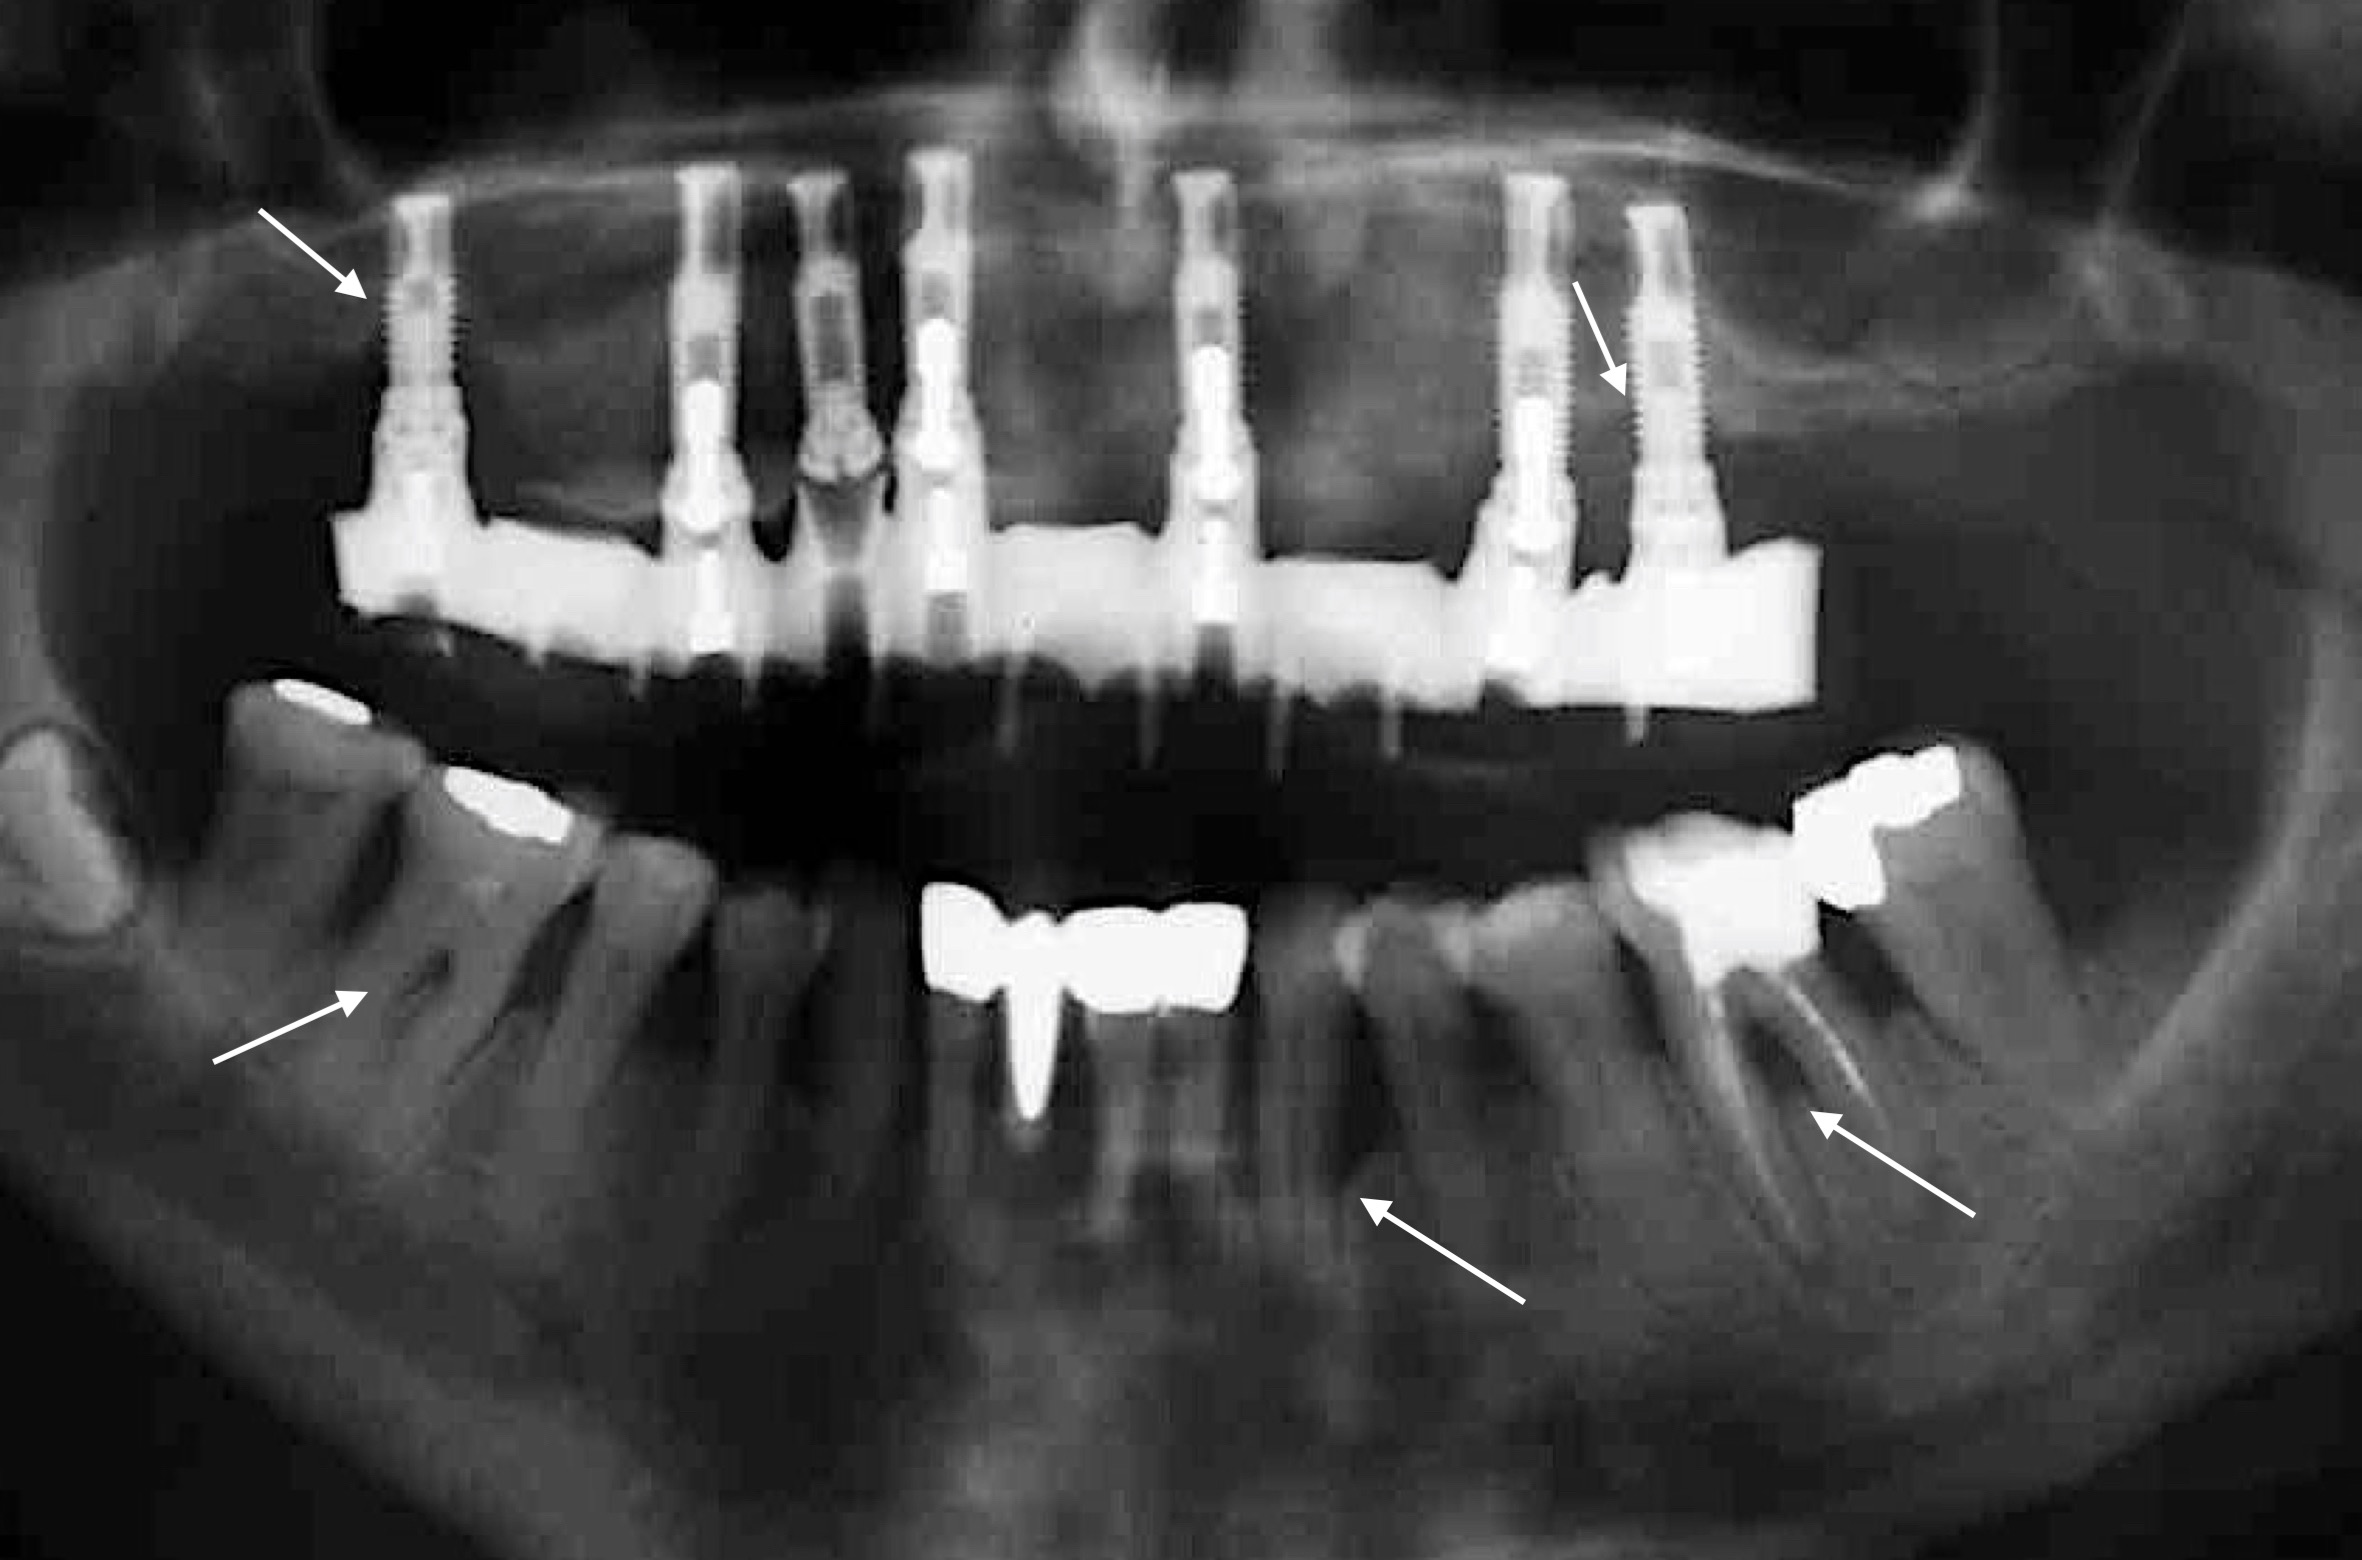

But just how great is the risk of periodontitis patients developing peri-implant mucositis or even peri-implantitis and, in the worst-case scenario, of experiencing implant failure compared with patients without periodontitis – smaller, the same or larger?

Numerous reviews from the last 10 years have shown that patients with underlying periodontal disease have a higher risk of implant failure (e.g. Renvert & Persson 2009, Sousa et al. 2016, and many others). In addition, this risk appears to be even higher among patients who have been diagnosed with generalized aggressive periodontitis (Monje et al. 2016). To avoid this complication wherever possible, the patient’s periodontal health must be maintained as strictly as possible. This means: 1) periodontal treatment must take place before implant treatment; 2) the patient’s oral hygiene must be rigorously optimized and, above all, the patient must be given precise new instructions after they have been fitted with their implant-retained prosthesis; 3) to prevent recurrence of the patient’s periodontitis and to enable early detection of peri-implant diseases, regular follow-up sessions must be scheduled and conducted; and 4) residual pocket probing depths should ideally be avoided after periodontal treatment! Why is the last point so important? A study from Australia (Cho-Yan Lee et al. 2012) showed very clearly that periodontitis patients with residual pocket probing depths (≥ 6 mm pocket probing depth) are at 4 to 5 times greater risk of developing peri-implantitis than periodontally healthy patients and periodontitis patients without residual pocket probing depths!

Nonetheless, we should not focus solely on the negatives, because periodontitis patients can of course achieve a high 10-year implant survival rate of approximately 92% (Zangrando et al. 2015).